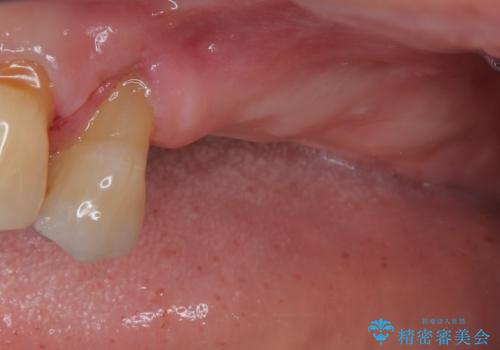

インプラントが待機期間に脱落することがありますが、一切のトラブルなく、最短期間で無事に治療を終えることができました。